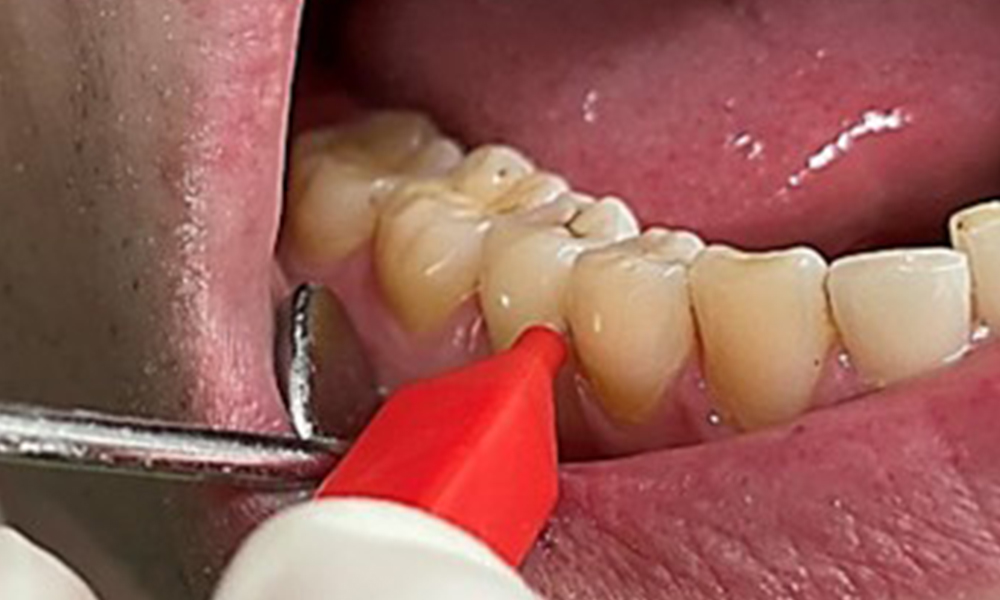

Discolouration caused by nicotine and tea consumption can be removed easily using an air polisher (Fig. 11).

Air polishing system use in the mandibular frontal lingual area (here, Proxeo Aura, W&H)

Fig. 11 Air polishing system use in the mandibular frontal lingual area (here, Proxeo Aura, W&H), © Dr R. Krapf

When using more abrasive powder, it is essential to work from a cervical to coronal direction and never point the outlet nozzle towards the gingiva to prevent potential emphysema. Good suction on the contralateral side is essential to reduce aerosol formation (Fig. 12).

Use of the air polishing system away from the sulcus with contralateral suction

Fig. 12 Use of the air polishing system away from the sulcus with contralateral suction, © Dr R. Krapf